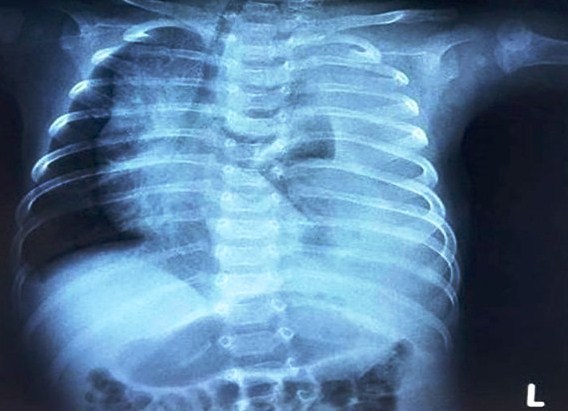

Bệnh viện Nhi đồng 2 TP.HCM cho biết, bệnh nhi nhập trong tình trạng khó thở nặng. Kết quả chụp X-quang phổi cho thấy một lỗ rò dấn đến tràn dịch màng phổi (dịch lỏng chưa rõ bản chất) bên trái lượng nhiều, gây nên tình trạng chèn ép nhu mô phổi khiến bé không thở được.

Phim X-quang cho thấy phổi bệnh nhi bị chèn ép do tràn dịch dưỡng chấp. Ảnh: BSCC